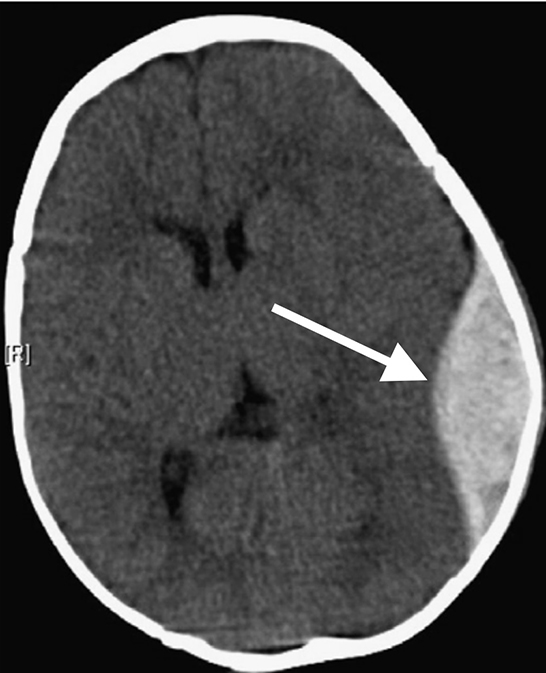

Epidural Hemorrhage

This is an Epidural Hemorrhage (EDH). This bleeding occurs between your skull and the outermost membrane that protects your brain. Bleeding that occurs between these layers is often described as a "lens" shaped on CT. Arterial bleeding is often the cause of this injury. Depending on the amount of blood, an operation may be required to remove the clot.